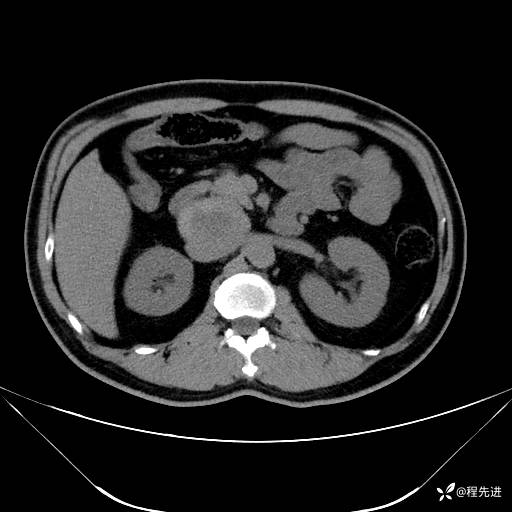

【腹盆】特别精彩病例|发现腹膜后肿物1月余

主诉:发现腹膜后肿物1月余

现病史:患者1月余前查体,行超声检查提示:后腹膜囊实性肿块;慢性胆囊炎伴胆囊内结石;无腹痛腹胀,不伴腹泻发热等;偶感腰背部酸痛。

CT平扫+增强: